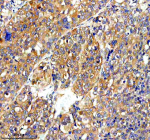

Immunohistochemical staining of RAPH1 using anti-RAPH1 antibody. RAPH1 was detected in a paraffin-embedded section of human breast cancer tissue. Heat mediated antigen retrieval was performed in EDTA buffer (pH 8.0, epitope retrieval solution). The tissue section was blocked with 10% goat serum. The tissue section was then incubated with 2 ug/ml rabbit anti-RAPH1 antibody overnight at 4oC. Peroxidase Conjugated Goat Anti-rabbit IgG was used as secondary antibody and incubated for 30 minutes at 37oC. The tissue section was developed using an HRP secondary and DAB substrate.